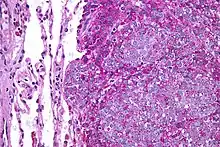

Histopathology

There are typically many small cells of the same size and appearance, with round nuclei.[3] Around half have extensive glycogen deposits, demonstrated with positive PAS staining.[3] Around 85% of Ewing sarcomas are positive for CD99, a cell-surface glycoprotein.[1] However, CD99 also occurs in some normal tissue and in other round cell sarcomas, as well as in lymphoblastic lymphoma and leukemia.[3] There may be keratin expression.[1]

Micrograph of a metastatic Ewing sarcoma with the characteristic cytoplasmic clearing on H&E staining, which was showing to be PAS positive

Micrograph of a metastatic Ewing sarcoma with the characteristic cytoplasmic clearing on H&E staining, which was showing to be PAS positive